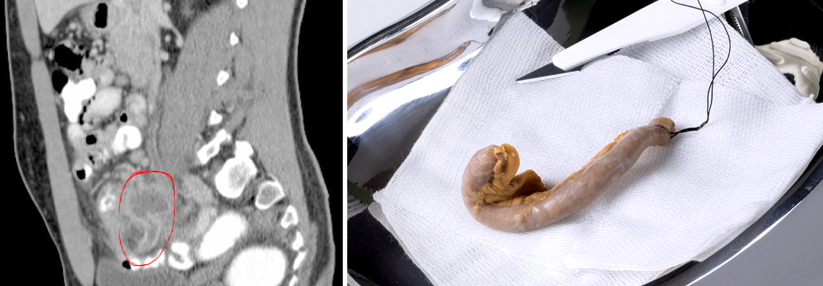

Die histologische Färbung der Appendix eines gesunden Patienten zeigt ein hohes Proteinase-K-resistentes alpha-Synuclein-Vorkommen (rot) der Mucosa. Eine Balkenlänge entspricht 100 μm. Die histologische Färbung der Appendix eines gesunden Patienten zeigt ein hohes Proteinase-K-resistentes alpha-Synuclein-Vorkommen (rot) der Mucosa. Eine Balkenlänge entspricht 100 μm. © Killinger BA et al. Sci Transl Med 2018; 10: pii: eaar5280

Ihre Erklärung stützen die Autoren auf die hohen Konzentrationen an intraneuronalem alpha-Synuclein, die sie im untersuchten Appendixgewebe von Gesunden nachweisen konnten. Darunter findet sich auch die pathologisch verkürzte Proteinform, die sich in den Gehirnen von Parkinsonpatienten in den sog. Lewy-Körperchen findet. Potenziell könnte die Appendix also ein Reservoir für das pathogene Protein darstellen, spekulieren die Autoren.

Die histologische Färbung der Appendix eines gesunden Patienten zeigt ein hohes Proteinase-K-resistentes alpha-Synuclein-Vorkommen (rot) im Querschnitt (links), in der Muscularis externa (oben) und der Mucosa (unten). Das Protein findet sich akkumuliert auch in den bei M. Parkinson auftretenden Lewy-Körperchen. Eine Balkenlänge entspricht 100 µm. Die histologische Färbung der Appendix eines gesunden Patienten zeigt ein hohes Proteinase-K-resistentes alpha-Synuclein-Vorkommen (rot) im Querschnitt (links), in der Muscularis externa (oben) und der Mucosa (unten). Das Protein findet sich akkumuliert auch in den bei M. Parkinson auftretenden Lewy-Körperchen. Eine Balkenlänge entspricht 100 µm. © Killinger BA et al. Sci Transl Med 2018; 10: pii: eaar5280